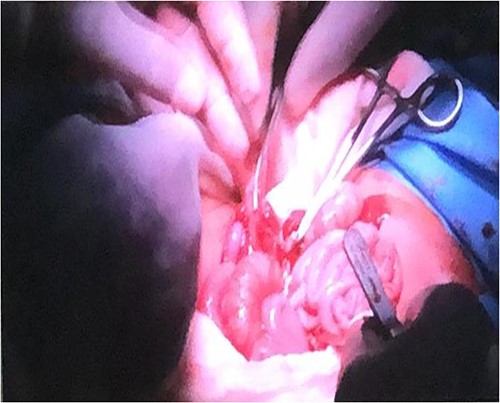

After anesthetic preparation and central line insertion, both twins were placed on sterile sheets and then prepped anteriorly, Incision was made using monopolar and bipolar diathermy in the connecting bridge, skin and muscle were cut, connections within parietal peritoneum were identified, and then carefully divided, followed by the connecting part of the liver (Fig. 2), after two and half hours of surgery the twins were finally separated and other twin was taken to another table.

Connections within parietal peritoneum were identified and then carefully divided, followed by the connecting part of the liver.